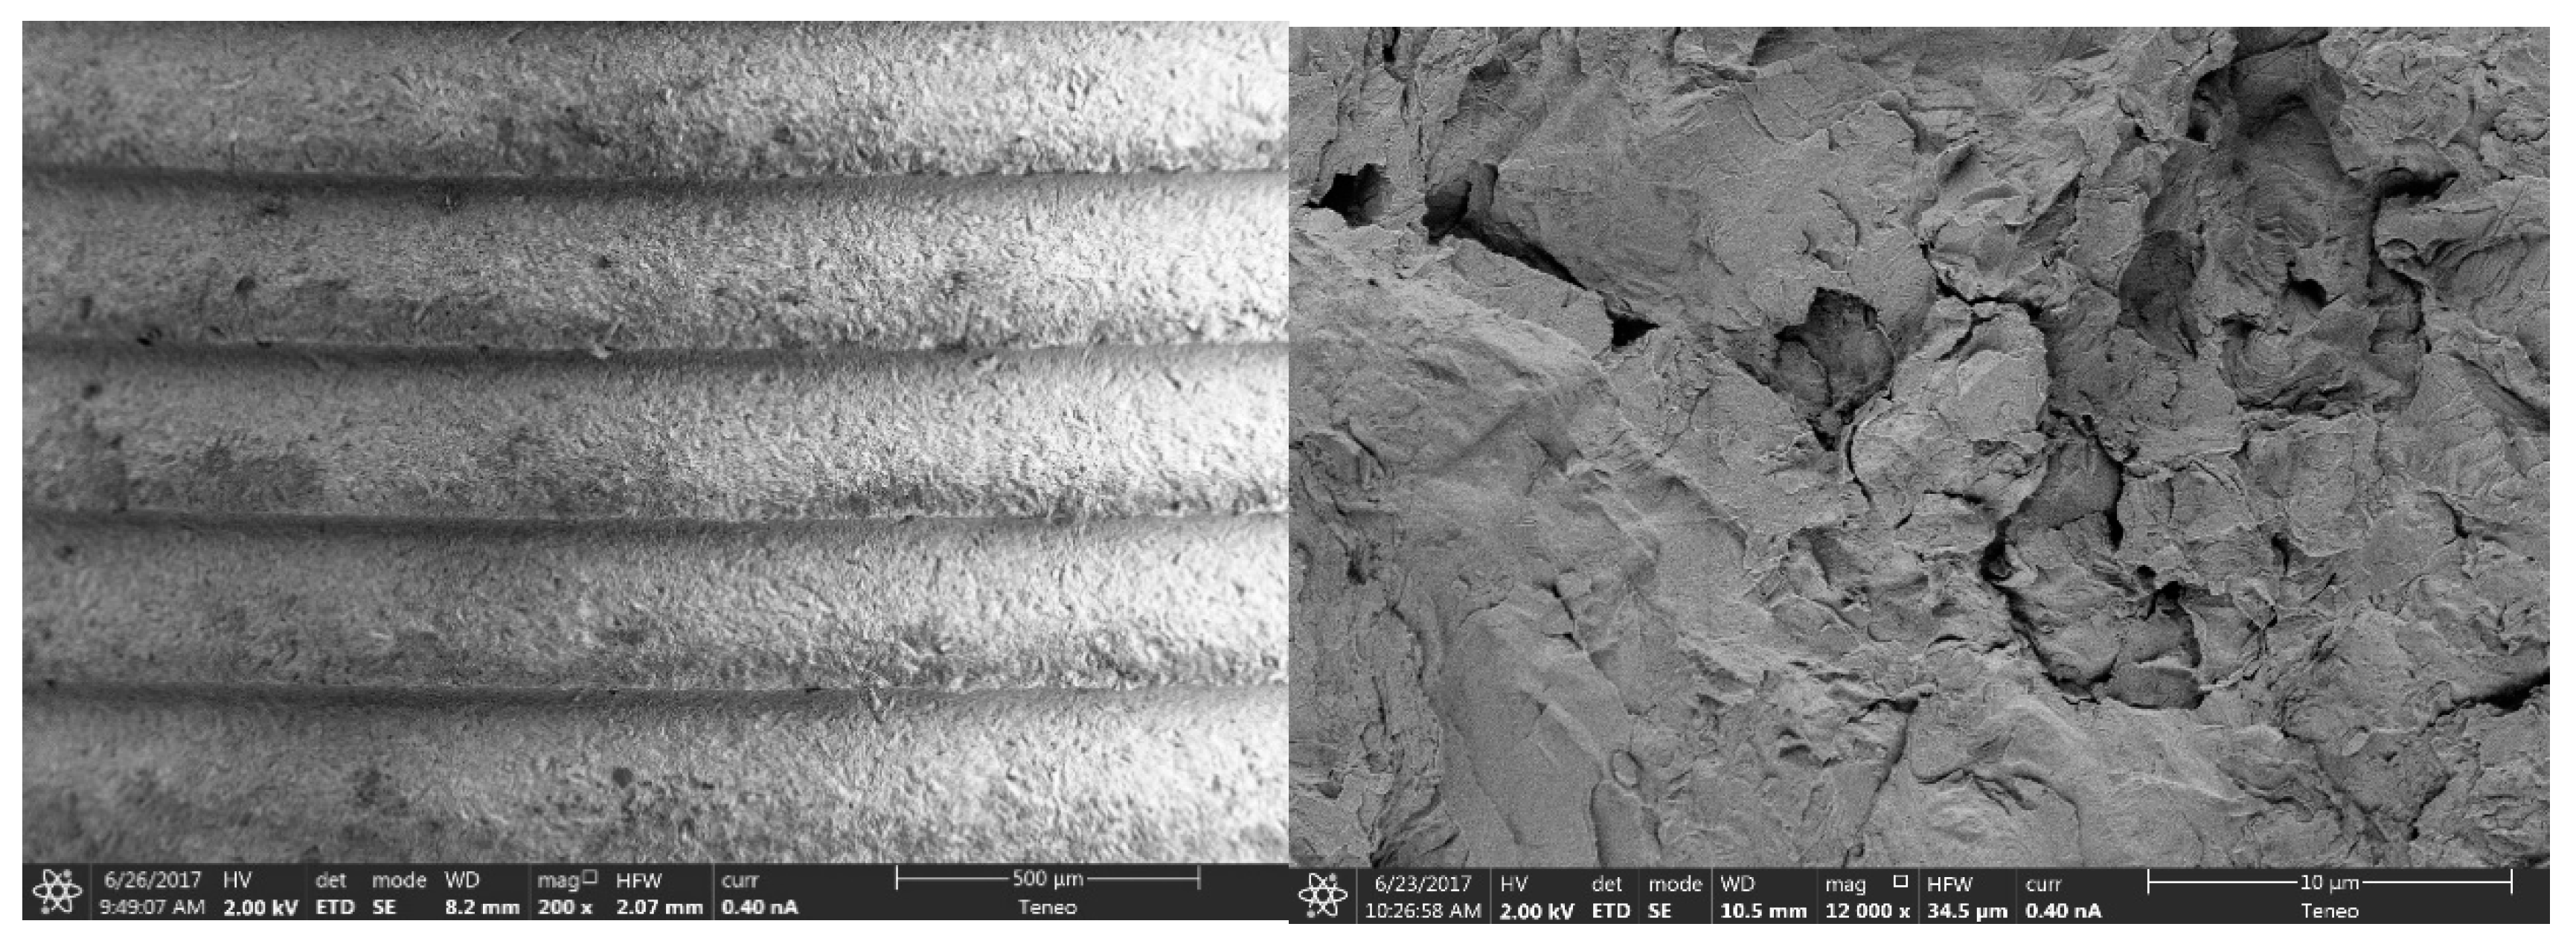

2.2.1. Morphological Analysis of the Surface

3.1.1. Morphological Analysis of the Surface